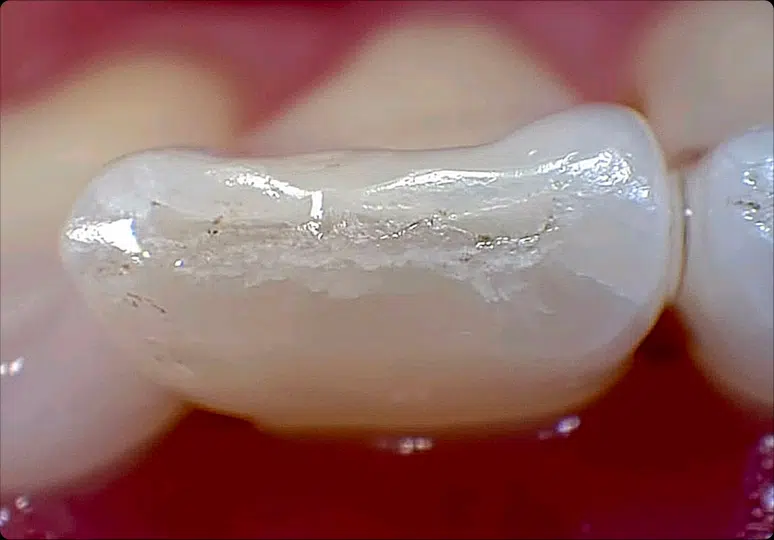

Intraoral Camera

Claris i5HD

25 years of intraoral camera evolution. Native 1080p HD sensor, space-grade anodized aluminum body, and less than 5% lens distortion. Turnkey integration with every major platform.